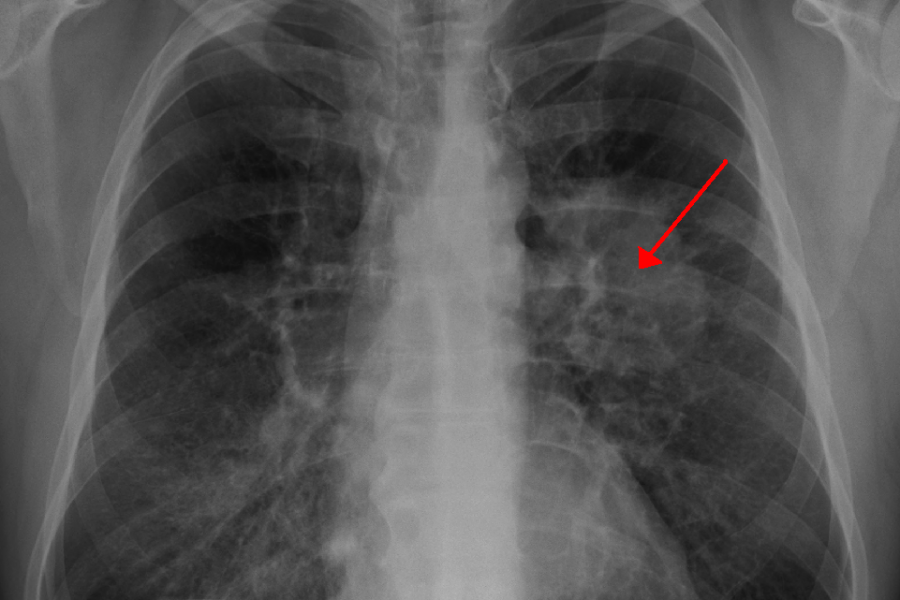

Xərçəngin bu növü əksər hallarda gizli inkişaf edir və bu xəstələliyə yoluxan şəxs onun əlamətlərinə o qədər də ömən vermir. Çoxları isə ağ ciyər xərçingi olduğunu başqa xəstəliyi ilə bağlı rentgen çəkdirən zaman öyrənir.

Oxu24.com  xəbər verir ki, türkiyəli mütəxəssisin məlumatına görə, kəskin ağ ciyər xərçənginin əsas səbəbi kimi tütün məmulatları göstərilsə də, araşdırmalar zamanı bu xstəlikdən əziyyət çəkənlərin 15 faizinin həyatları boyu siqaretdən istifadə etmədiyi bəlli olub. Genetik faktorlar, asbest, radon qazı, havanın çirklənməsi, içmə suyundakı yüksək səviyyəli arsenik maddələr səbəbiylə bu risk altında olan şəxslər həyat şərtlərini yaxşılaşdırmaqla bu riski minimuma endirə bilərlər. Eyni zamanda ağ ciyər xərçəngi vaxtında aşkar edildikdə tam müalicə edilə bilər. Xəstəliyin əsas əlamətli isə aşağıdakılardır: Davamlı nəfəs darlığı və xırıltılı nəfəs. Keçməyən öskürək və qatı bəlğəm. İştahsızlıq və çəkinin itirilməsi. Sinə, kürək, bel, külək sümüyü, qol və ayaq ağrısı. Səsin batması. Udqunmaqda çətinlik. göz qapağının sallanması. Təkrarlanan infeksiyalar. Barmaqların keyiməsi.